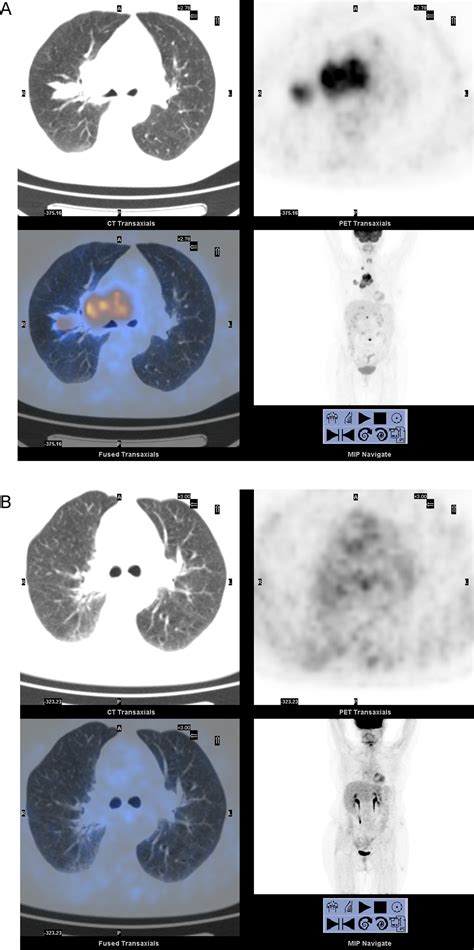

• Accurate Staging: The detailed images provided by PET-CT scans help in accurately staging the cancer, which is crucial for determining the appropriate treatment plan. Staging involves assessing the size and extent of the tumor, as well as whether it has spread to other parts of the body.

• Treatment Monitoring: PET-CT scans can be used to monitor the effectiveness of treatment by comparing images taken before and after therapy. This helps in adjusting treatment plans as needed.

Interpreting the results of a PET-CT scan involves a detailed analysis by a radiologist. The images are reviewed to identify areas of high metabolic activity, which may indicate the presence of cancer. The results are then shared with the patient's healthcare team, who will discuss the findings and develop a treatment plan. It is important to note that while PET-CT scans are highly accurate, they are not foolproof. False positives and false negatives can occur, and additional tests may be needed to confirm the diagnosis.